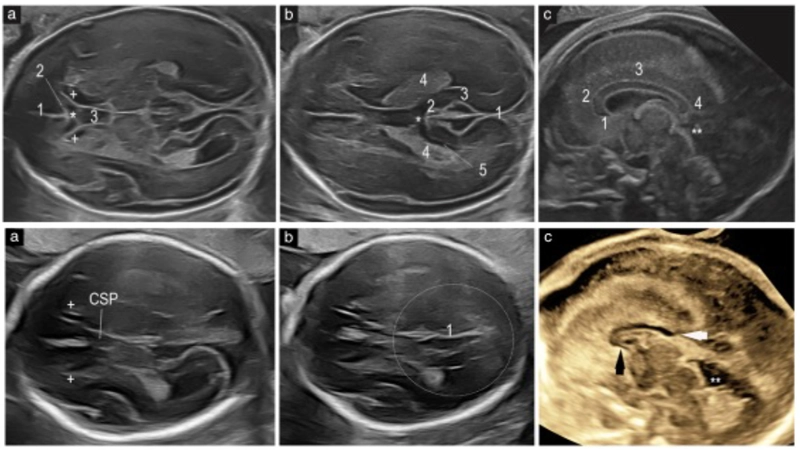

Ecografía